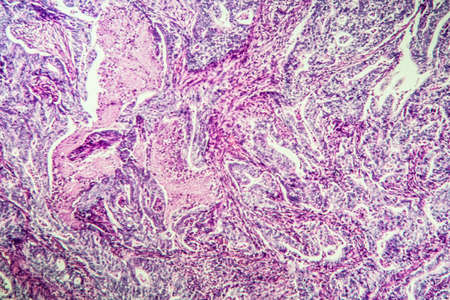

Breast cancer of the woman diseased tissue 100x